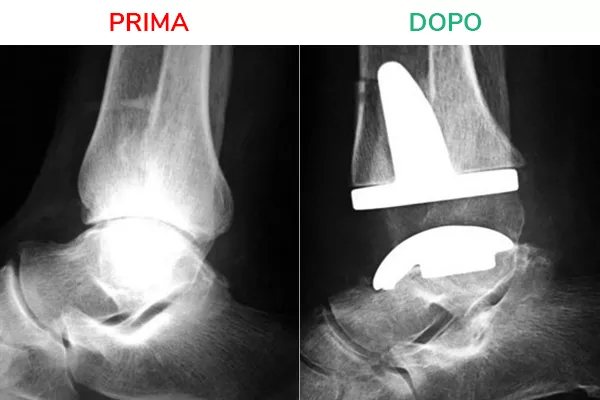

Radiografia in movimento

La radiografia in movimento mostra lo spazio articolare ripristinato e la distanza tra tibia e astragalo. Il movimento risulta fluido e scorrevole, simile a quello fisiologico. Il risultato che si deve ottenere al termine dell’intervento di Protesi di Caviglia è la normale mobilità della caviglia in flesso-estensione.